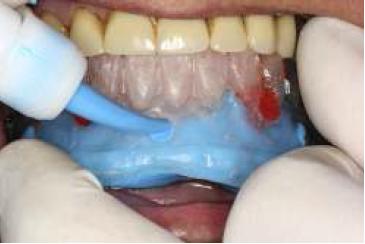

La guía multifuncional debe presentar 3 orificios en el flanco vestibular bajo el talón de los dientes para inyectar silicona monofásica al momento de la impresión, y adicionalmente debe poseer otros 2 orificios a la altura del incisivo lateral/canino de la cara vestibular para unir la guía con los transfer previamente ferulizados entre sí. Con el paciente en oclusión se ferulizó la guía a los transfer con acrílico, a través de los orificios ubicados entre lateral y canino. Se esperó la polimerización del acrílico en oclusión. Luego se inyectó silicona monofásica por los 3 orificios destinados para ello (fig. 11). Se solicitó a la paciente que ubicara su lengua en íntimo contacto con la cara lingual de la guía, esto sirve como contención para el material de impresión. Se esperó la polimerización, se retiró la impresión y se evaluó.